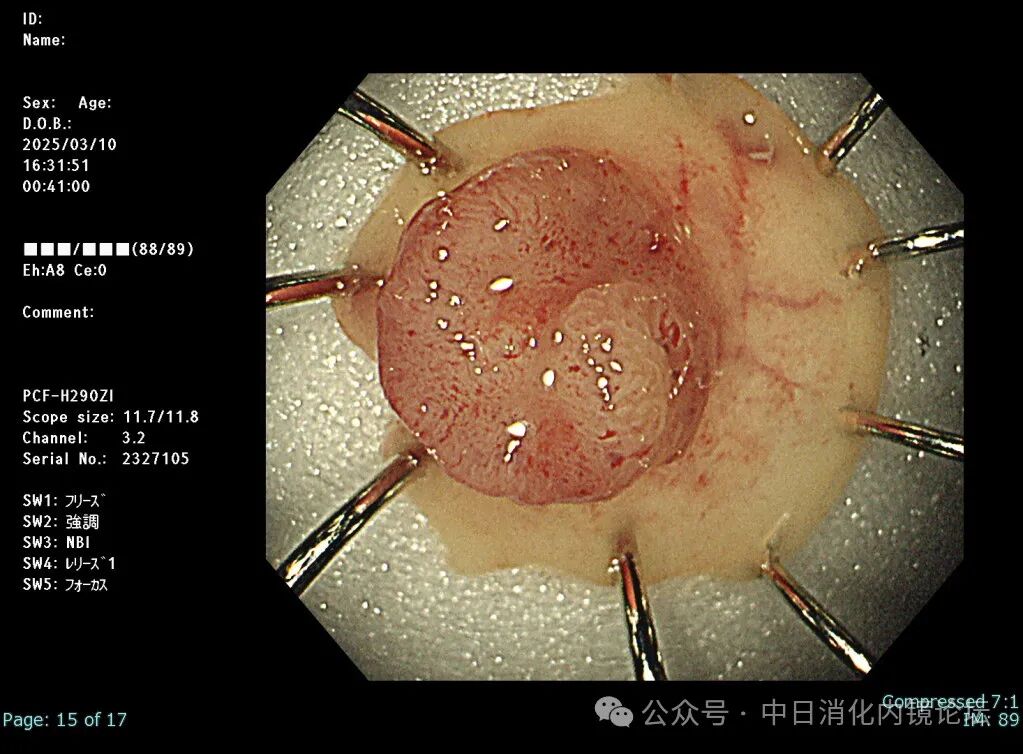

在繁忙的临床工作中按照日本消化内镜学会倡导的病变观察流程,便可事半功倍,极大地提高诊断准确性和检查效率。病变观察远景→近景→放大,白光→NBIJNET→靛胭脂 pit pattern。切除后创面确认,确保无残留,断端阴性→肛侧腹侧点墨标记→标本固定,为病理诊断以及今后可能的追加治疗提供完整精确的原始资料。